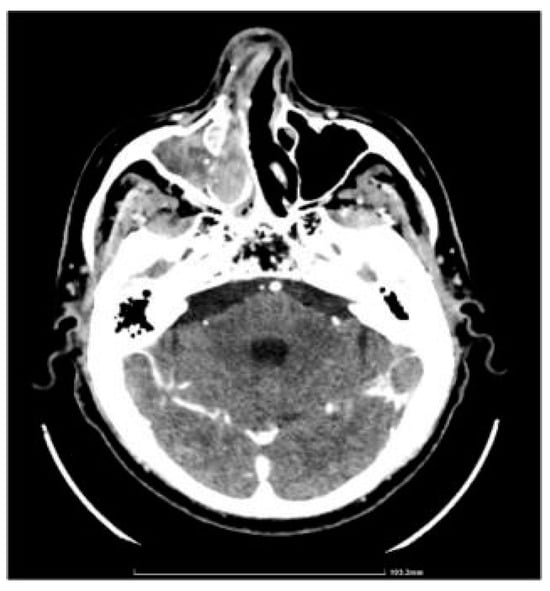

CT showed complete fluid and parafluid accumulation in the right maxillary sinus, with medial sinus wall resorption and antero-lateral walls osteosclerosis, extension of the inflammatory process through the right ostiomeatal complex at the ethmoid cells level as well as at the right frontal sinus level which was completely occupied; this was accompanied by discrete iodophilic right nasal polyposis and thickening of the mucosa at the right sphenoidal sinus level (Figure 2 and Figure 3).

Figure 2.

CT axial section.